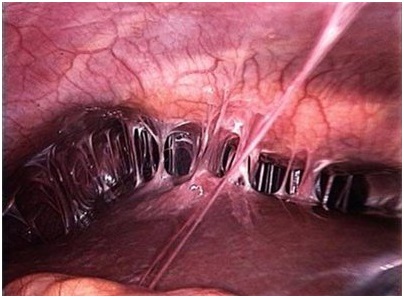

Лапароскопия. Этот метод не только помогает определить наличие спаек, но и позволяет их удалить. Процедура заключается в том, что врач делает небольшой разрез на животе пациентки и вводит лапароскоп — устройство с видеокамерой и инструментом для удаления спаек. В брюшную полость подается углекислый газ, что обеспечивает лучшую видимость для врача.

Лапароскопия является последним вариантом лечения. Она становится необходимой, когда спайки имеют длительный характер и другие методы не приносят результата. Нежелательные соединения просто разрезаются с помощью лапароскопа. Однако этот метод подходит не для всех и может сопровождаться осложнениями.